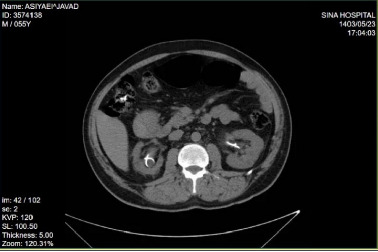

双J (DJ)支架置入术相关的并发症有很好的文献记载,但DJ支架打结仍然是一个极其罕见的事件。我们提出了一个独特的情况下,一个打结和结壳的DJ支架,以及对这一罕见并发症的文献回顾。一名55岁男性,因结石导致输尿管梗阻,最初采用经皮肾造口术(PCN)和DJ支架置入术。患者出现在支架移除的延迟随访后。尽管成像显示没有结痂或打结的证据,膀胱镜尝试移除支架失败。进一步的评估,包括输尿管镜检查,发现DJ支架在肾盂处有明显的结痂和打结。使用半刚性输尿管镜和碎石成功取出支架,无需开放手术。该病例强调了早期随访和患者依从性对预防此类并发症的重要性。当单纯牵引不能取出DJ支架时,应采用先进的内镜技术,如碎石和输尿管镜检查,以有效地处理复杂病例。

Complications related to double J (DJ) stent placement are well documented, but DJ stent knotting remains an exceedingly rare event. We present a unique case of a knotted and encrusted DJ stent, alongside a review of the literature on this rare complication. A 55-year-old man with a history of ureteral obstruction due to stones was managed initially with percutaneous nephrostomy (PCN) and DJ stent placement. The patient presented after a delayed follow-up for stent removal. Despite imaging showing no evidence of encrustation or knotting, cystoscopic attempts to remove the stent failed. Further evaluation, including ureteroscopy, revealed significant encrustation and knotting of the DJ stent at the renal pelvis. The stent was successfully removed using a semirigid ureteroscope and lithoclast without open surgery. This case highlights the importance of early follow-up and patient compliance in preventing such complications. When simple traction fails to remove a DJ stent, advanced endoscopic techniques such as lithotripsy and ureteroscopy should be employed to manage complex cases effectively.